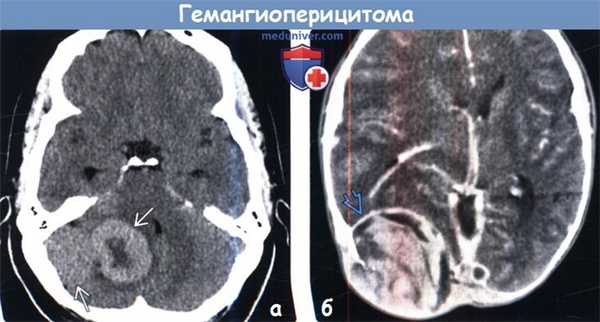

(а) Бесконтрастная КТ, аксиальный срез: в задней черепной ямке определяется гиперденсное объемное образование с локальным масс-эффектом. При резекции была диагностирована анапластическая гемангиоперицитома III степени злокачественности по классификации ВОЗ (grade III).

(б) КТ с контрастированием, аксиальный срез: в затылочной области определяется объемное образование с гетерогенным характером контрастирования и протяженной эрозией кости. Обратите внимание на перифокальный отек и масс-эффект. Локализация и внешние признаки характерны для гемангиоперицитомы. Эти редкие опухоли характеризуются высокой частотой рецидивирования и частым метастатическим поражением за пределами ЦНС.

2. КТ при гемангиоперицитоме (ГПЦ):

• Бесконтрастная КТ:

о Гиперденсное внемозговое объемное образование с перифокальным отеком

- Часто присутствуют участки кистозной и некротической трансформации с низкой КТ-плотностью

о Может наблюдаться эрозия костей свода черепа

о Са++ или гиперостоз отсутствуют

• КТ с контрастированием:

о Интенсивный гетерогенный характер накопления контрастного вещества